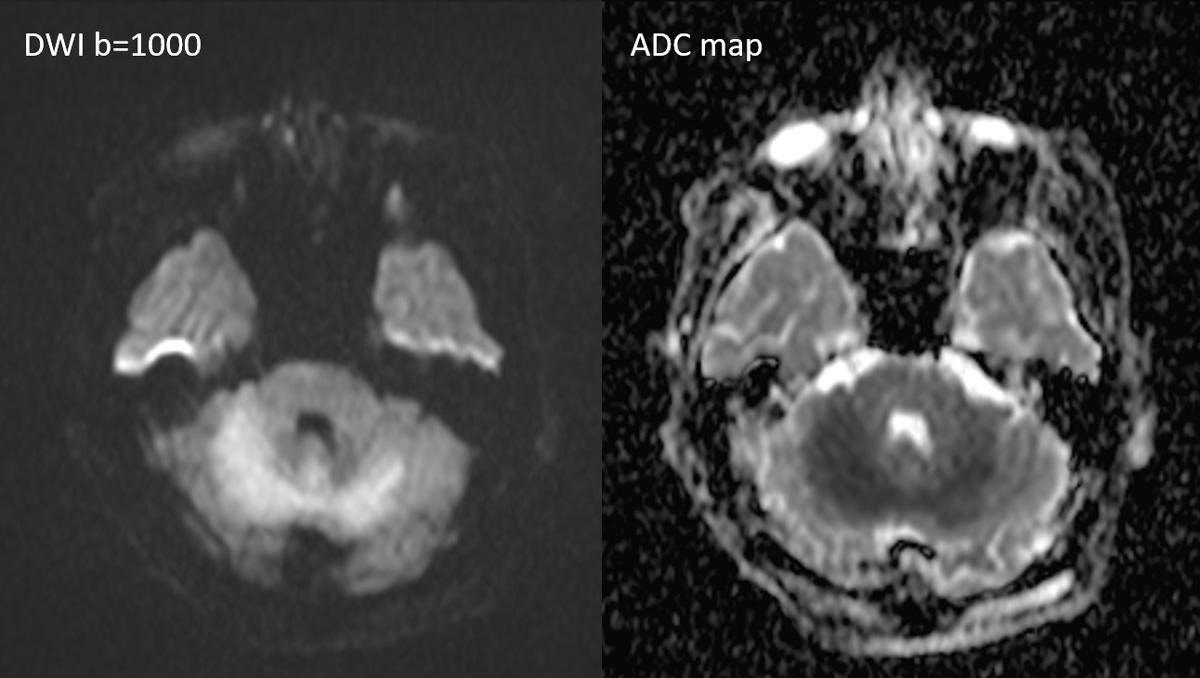

症例1:28歳男性

- 4か月ほど前から歩行時の息切れあり、1か月前から下肢の疼痛が出現、1週間前からはベッド上で生活していた。

- 3日前から呂律が緩慢となり、増悪したため、父親が救急要請。